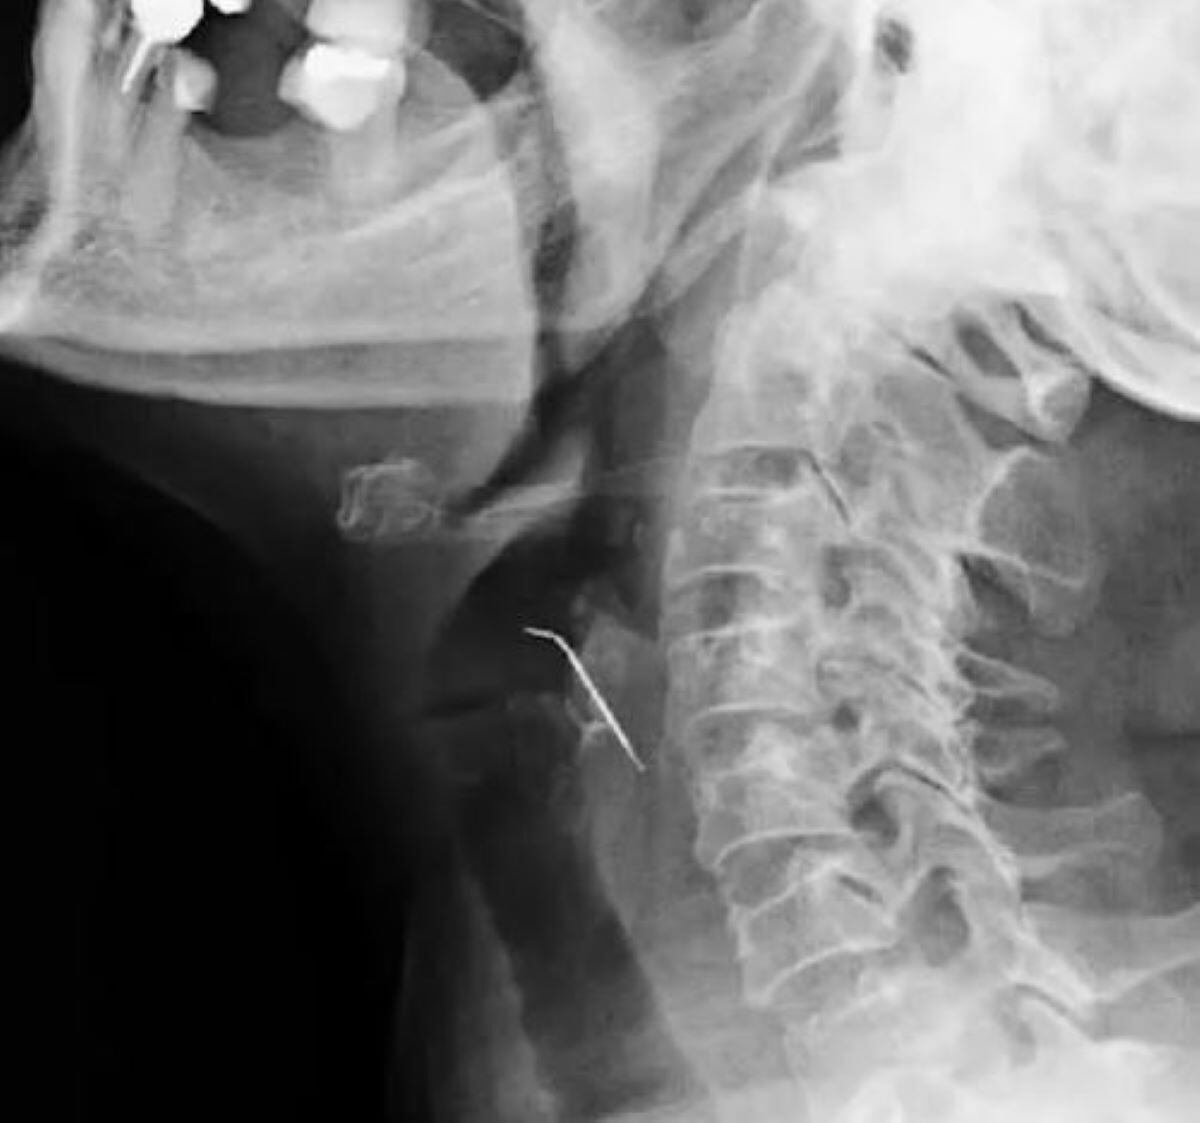

Uma mulher de 68 anos procurou um hospital ao sentir fortes dores na garganta, após exames, os médicos descobriram um prego perfurando a artéria carótida. O caso foi registrado em fevereiro no Peru.

• Mulher come carne moída e quase morre após ficar com prego preso na garganta